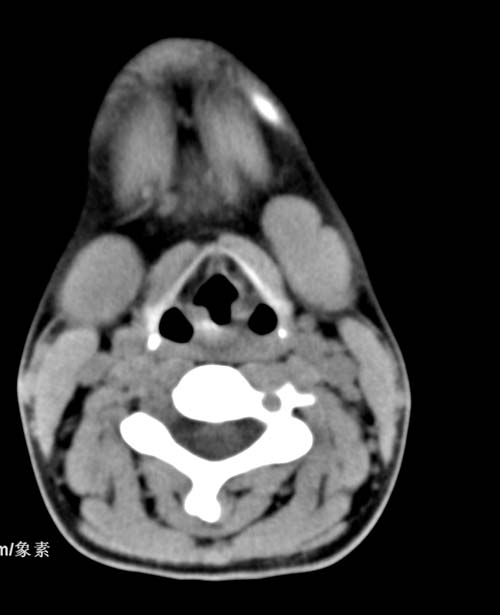

标题: CT22662:女 23 自述双侧颌下腺肿大年余 近来疼痛 左侧明显 [打印本页]

标题: CT22662:女 23 自述双侧颌下腺肿大年余 近来疼痛 左侧明显

见双侧颌下腺略肿大  未见结石及钙化 考虑双侧慢性炎症 ?请指教